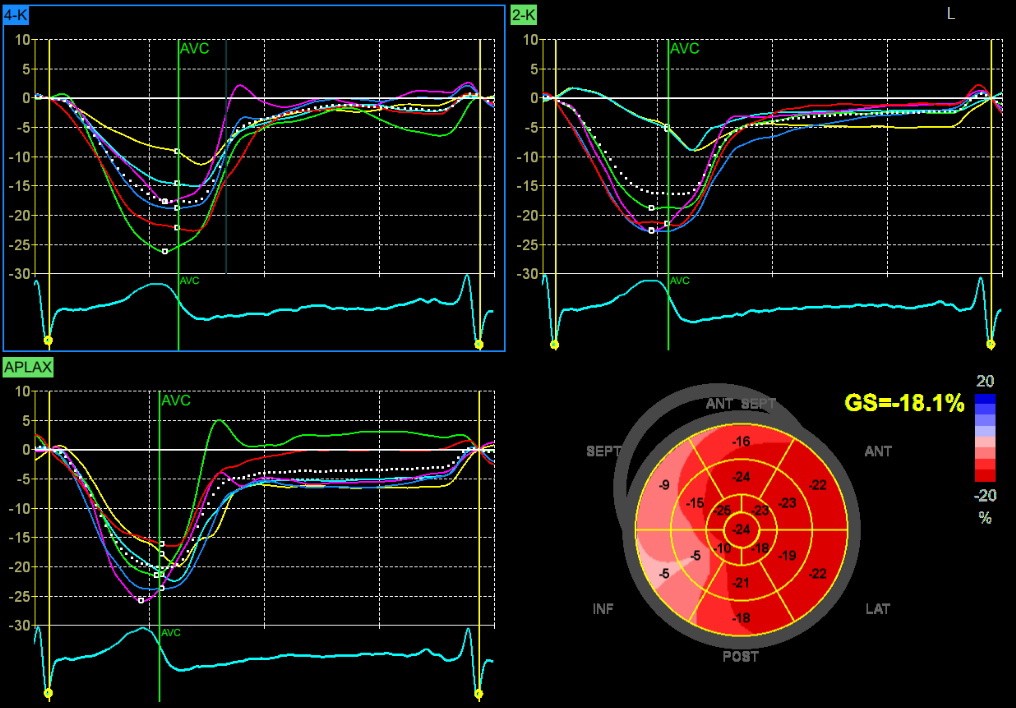

EF 15%, GLS severely reduced,

Dispersion 109ms

EF 15%, GLS severely reduced, Dispersion 109ms